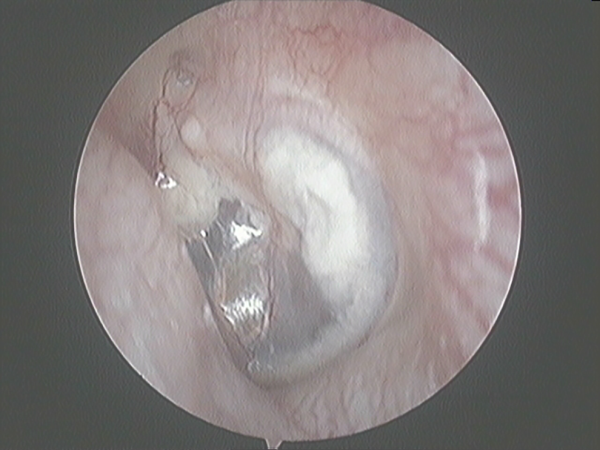

Complete perforation closure was evident in 117 (82.39%) of the 142 ears after primary FG myringoplasty. Surgery failed in 25 (17.61%) ears, mostly because of microperforations affecting <10% of the surface of the eardrum. In these patients, a second attempt of FG myringoplasty was offered 12 months after the first failed surgery. This procedure was performed successfully in 13 ears. Thus, our global success rate including the results from the revision surgery was 130 (91.55%) of 142 (Table 1).

Success closing the perforation was found in 87.17% of <25%-sized perforations, 93.87 of 25% to 50%-sized perforations, 94.11% of 50% to 75%-sized perforations, and 90% of 75% to 100%-sized perforations, a nonsignificant difference (χ2 test P = .21). The closure rate did not differ significantly between anterior perforations and those in other locations. There were 4 failures in the anterior location and 9 failures in the rest of locations (Fisher exact test, P = .575).